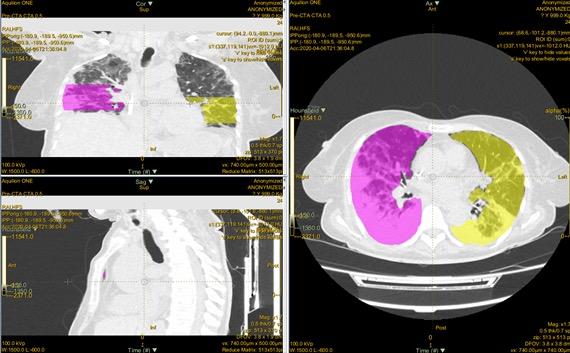

Figura 2: Representação dos processos de segmentação e volume das imagens para posterior extração de características radiómicas (imagem do autor)

O processo de segmentação desenvolveuse por várias etapas, desde a criação inicial de contornos, à obtenção do volume de interesse até à exportação de características radiómicas destas imagens. Procedeu-se à segmentação de porções pulmonares, onde existiam áreas de maior lesão. Isto porque na realização da segmentação da totalidade do pulmão surgiram constrangimentos computacionais que limitavam o estudo. Assim, optou-se pela utilização de fatias de 50 mm, para pulmão direito e esquerdo. Apesar de resultados promissores da utilização das características radiómicas, a análise de textura ainda não passou à prática clínica por várias razões, incluindo a compreensão limitada do significado biológico das características texturais medidas, a falta de evidência do significado das características texturais em comparação com os estudos convencionais e o insuficiente controlo de resultados. O uso das características radiómicas na prática clínica tem sido dificultado pela indisponibilidade de modelos radiómicos amplamente validados. A identificação de modelos robustos é também dificultada pela variabilidade das características em função dos dispositivos de aquisição de imagem e dos diversos protocolos de

Figura 3: Imagens representativas na aplicação LIFEx, onde se visualiza as áreas segmentadas nos campos pulmonares e sua localização. A partir desta aplicação é realizada a análise textural e a extração de características radiómicas (Imagem do autor).